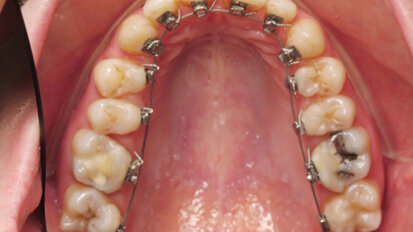

Bělení zubů a ortodoncie

St. 9. září 2020